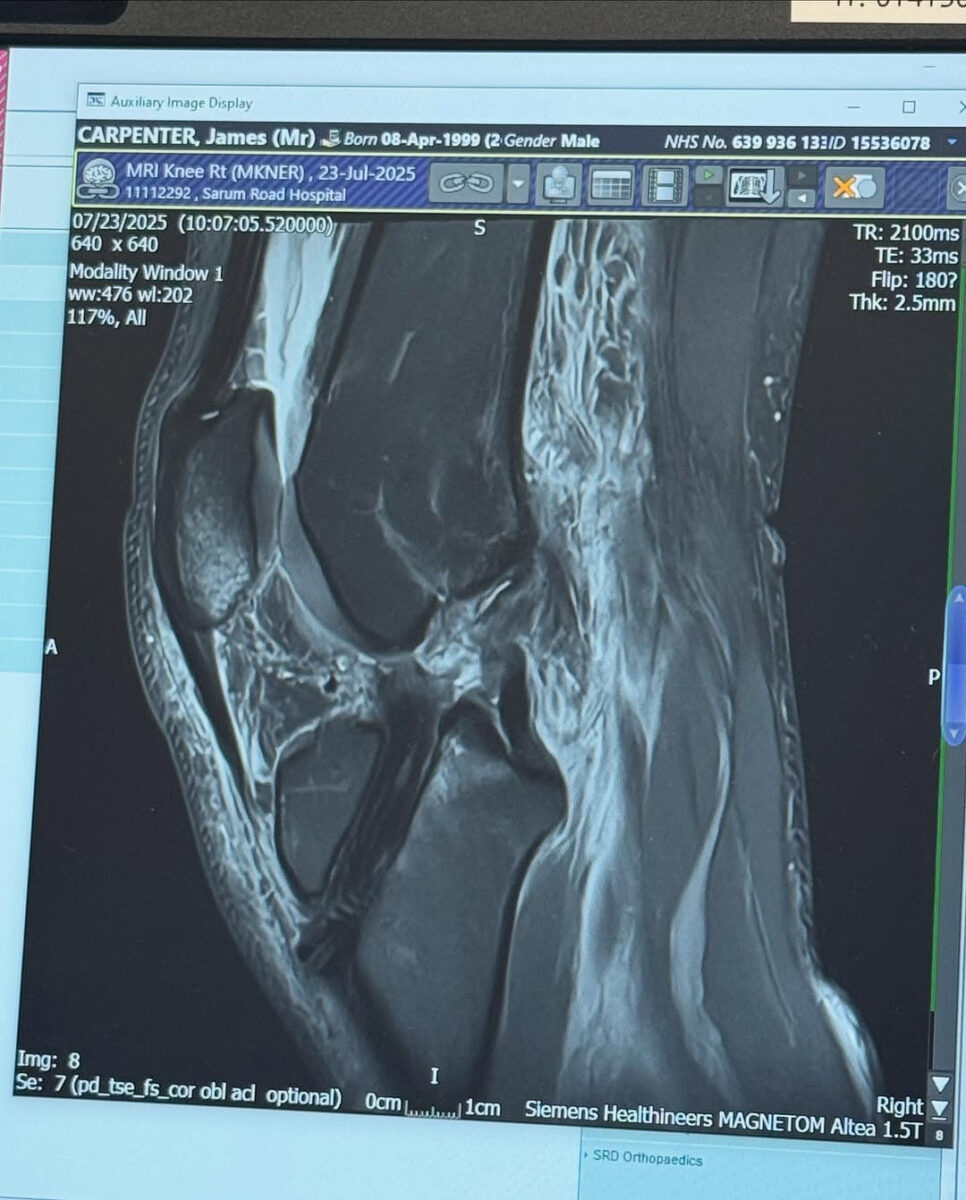

“Fresh out of surgery from my third ACL reconstruction, second time on this knee eight years apart. This time a bit more complicated due to the previous injury having to remove the previous graft that was hanging around in there and needing a different type of graft due to already having a hamstring graft out of both legs. I’ve also had a LET’s procedure involving extra reinforcements down the outside of the knee that will provide more stability.